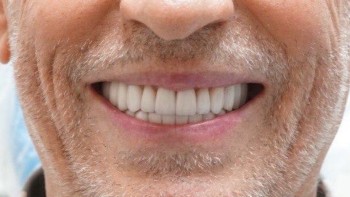

Ведерникова Елена Леонидовна принимает в «ЦЕНТР ГНАТОЛОГИИ ЕЛЕНЫ ВЕДЕРНИКОВОЙ» в Ростове-на-Дону. Главный врач, врач высшей категории, стаж 29 лет. Специализируется на ортодонтии и гнатологии, по которым клиника оказывает 4 услуги. Имеет 5 работ до/после в портфолио. Квалификация специалиста подтверждена 5 лицензиями, сертификатами и наградами. Для уточнения дополнительной информации о специалисте или записи на прием можно позвонить по телефону

5 работ в портфолио

Владеет всеми новейшими американскими технологиями создания голливудской улыбки. Совместно со специалистами Бостонского института проводит комплексное лечение по принципам нейромышечной и эстетической стоматологии, заболеваний височно-нижнечелюстного сустава.